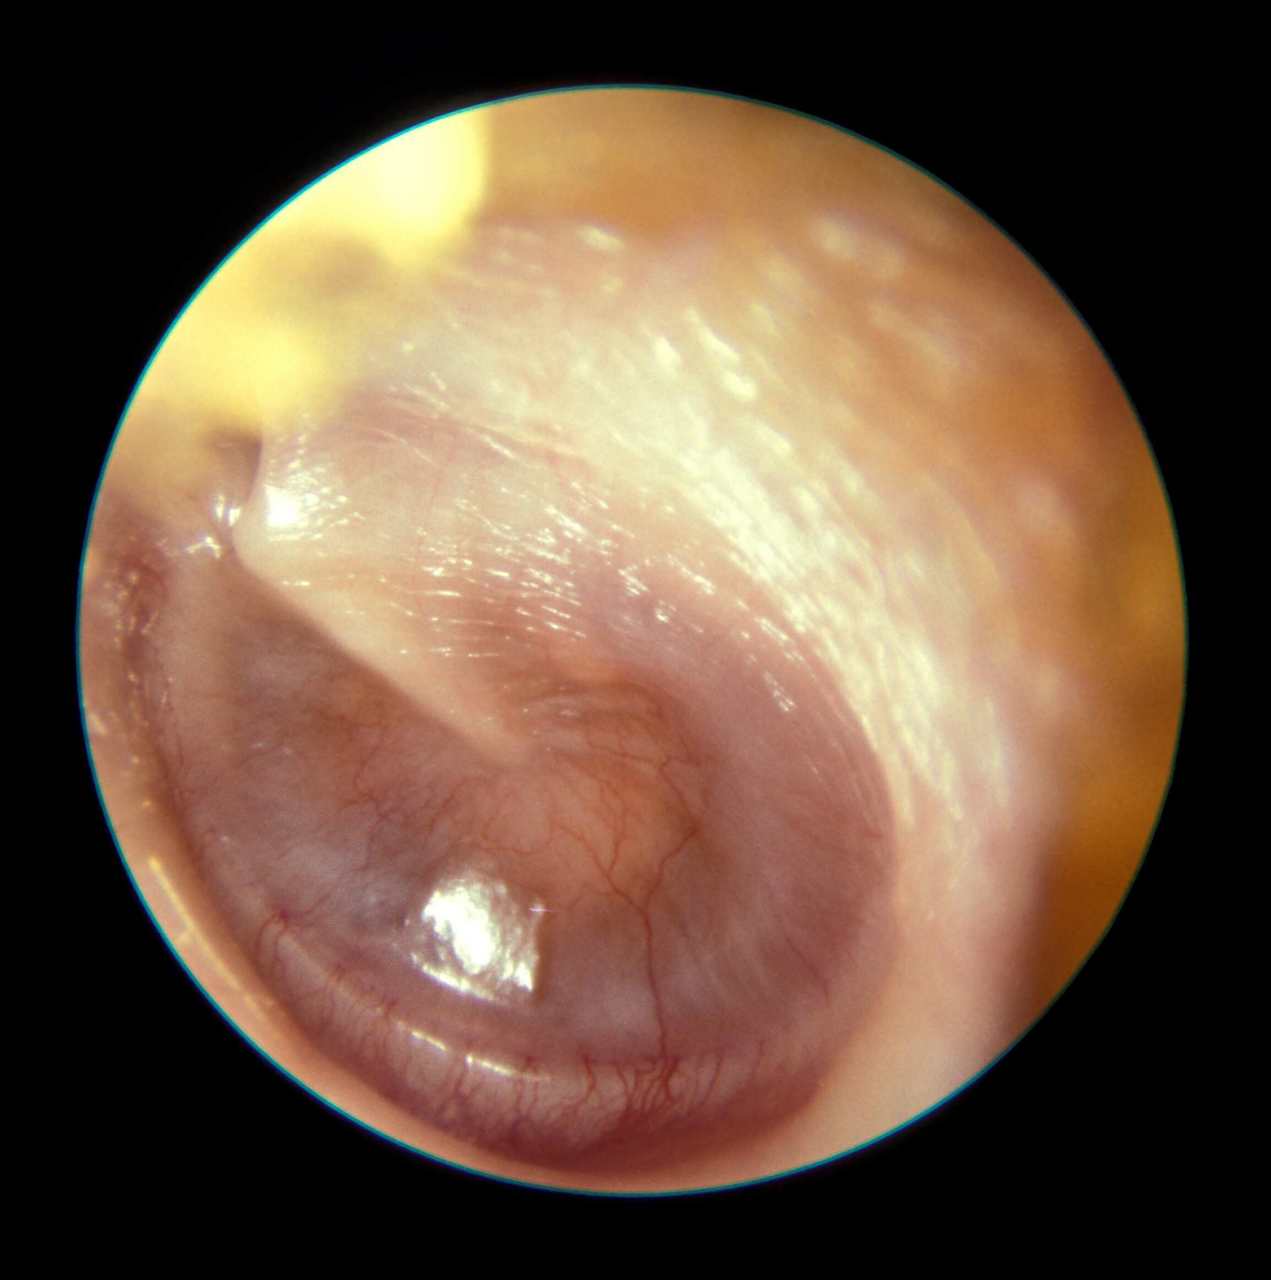

Voici son tympan à gauche.

Question 4 : Qu’en pensez-vous ?

Vous examinez le patient. Il n’y a pas d’autre atteinte des paires crâniennes, hormis un nystagmus discret. Il n’a pas de vertiges et semble entendre des deux oreilles. Vous ne retrouvez pas d’érythème migrant. Il n’y a pas de vésicules dans le conduit ou sur le tympan, ni d’éruption de la zone de Ramsay-Hunt. Vous retrouvez sur le tympan gauche une petite poche de rétraction sans complication. Le tympan droit est anormal et vous suspectez une surdité de transmission.

Question 9 : Que pouvez-vous dire du tympan ?

C’est une otite chronique avec inflammation du tympan

C’est la grosse masse blanchâtre derrière le tympan

C’est une otite chronique avec un cholestéatome : il a donc une inflammation

Otite moyenne aiguë droite

On voit le tympan dans la partie inférieure, ce n’est pas une perforation du tympan

Rappel sur ce qu’est un cholestéatome. Il y a normalement à l’intérieur de la caisse du tympan uniquement de la muqueuse. Lorsqu’une poche de rétraction du tympan (donc une poche qui est aspirée dans la caisse) se perce, on se retrouve avec de la peau à l’intérieur de la caisse. Cette peau s’accumule et par une réaction chimique locale (ce n’est pas une invasion tumorale) entraîne une lyse progressive de contact des structures osseuses.

Vous diagnostiquez donc un cholestéatome de l’oreille droite.